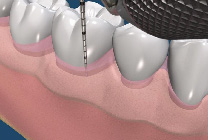

由於顯微鏡具有高倍率的放大效果,並提供卓越的強化光源,牙科的治療都相當微小,一般的放大鏡可放大約2-8 倍,而顯微鏡大約可放大約 30-40 倍,讓整個治療過程可以持續擁有清晰的視野,所以,顯微治療技術相較於傳統治療,最直接的突破即在於大大地提昇了醫師雙眼的透視能力,使得極細微的組織結構都能夠明顯的被呈現出來。因此,藉由這樣的特性,當顯微鏡被應用在根管治療上,便成為絕佳的利器,可以讓原本難以尋找的根管入口在顯微鏡下無所遁形,而原本錯綜複雜的根管系統也不再是一個讓人無法探索的區域。(圖01~03)

圖1